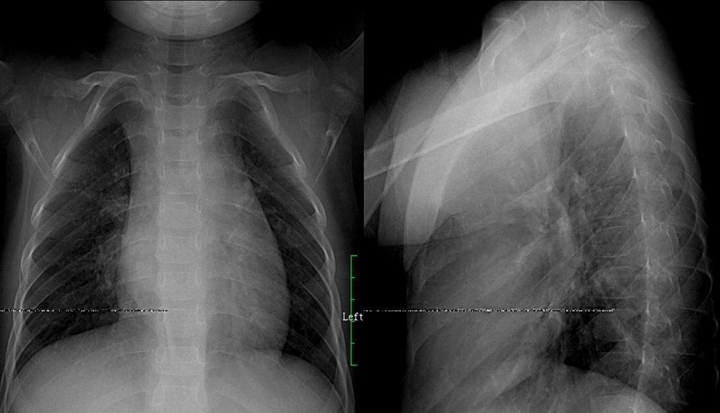

肺結(jié)核:肺結(jié)核分五類型,原發(fā)血播浸結(jié)其,原發(fā)肺內(nèi)淋巴引,血播急粟三均勻,慢播新老病灶模糊,浸潤滲出片絮球,慢纖空洞蜂窩柳,胸膜炎見結(jié)核多,確定三期療效后估,臨床影征痰檢為依據(jù),菌量毒性免疫力,鑒別診斷炎性先,肺癌轉(zhuǎn)移假瘤辨。備注: 蜂窩柳---一形如蜂窩狀肺紋理呈垂柳征。

原發(fā)支氣管肺癌:肺癌起源支上皮,組織大體類型別,中央肺癌四征像,不張氣腫腫塊肺炎,周圍小癌邊模糊,增大濃密邊清楚,癌腫壞死空洞偏,臍凹兔耳癌索現(xiàn),彌漫肺癌肺泡間,粟粒結(jié)節(jié)重疊囊。